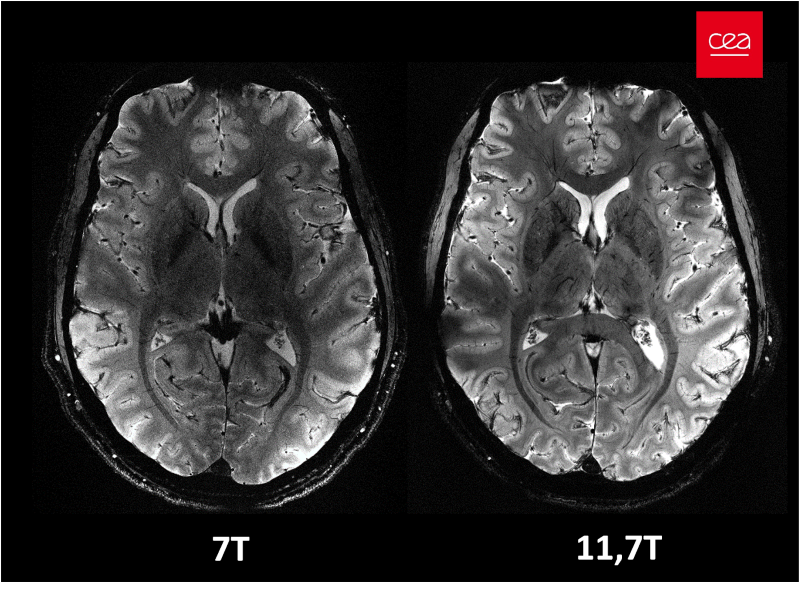

Abstract #4895. - Opening new horizons with the first human brain in vivo experiments at 11.7T:

Abstract #523.

In vivo imaging of the human brain with the Iseult 11.7-T MRI scanner

Nature Methods. 2024. doi: 10.1038/s41592-024-02472-7.

First in vivo images of the human brain revealed with the Iseult 11.7T MRI scanner

Opening New Horizons With The First Human Brain In Vivo Experiments At 11.7T

Proceedings of the ISMRM 2024, Singapore, p0523.